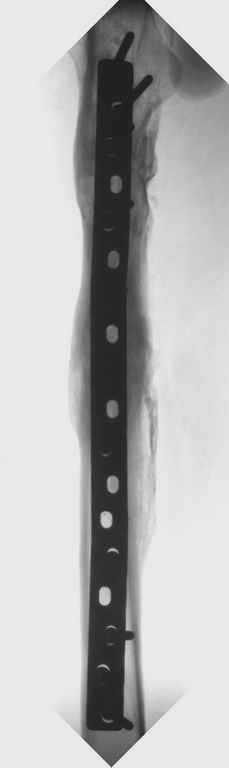

Можно применить гвоздь с множественными косыми остеотомиями, но я посчитал, при применении 4.5 мм длинной пластины или L-образную пластину с короткой ножкой в шейку, шанс на удержание отломков более вероятная, чем гвоздем.

Двойную остеотомию при лечении можно делать так: латеральным субвастус доступом (с приподниманием вастус латералис) обнажается латеральная поверхность бедра, заранее сделанным преоперационнным планом определяется место остеотомии, периостиум обнажается только по этому

плану, т.е. по линии остеотомии. Перед остеотомией накладывается дистракционный аппарат, делается остеотомия и медленная дистракция, накладывается по длине пластина, дистракция и компрессия по

необходимости, фиксируются проксимальный и дистальный концы пластины 4.5 мм шурупами, косо для стабильности, затем работа с медиальным

фрагментом.

Необходимо создание медиальной компрессии, которая создастся с помощью коротких шурупов против латерального кортекса. Чтобы эти шурупы не выпали из дырок на пластине, надо применить резьбовую шайбу Schulle nut, который имеет резьбу точно подходящую к резьбе шурупа, и ставится с внутренной стороны пластины, те конструкцию locking plate.